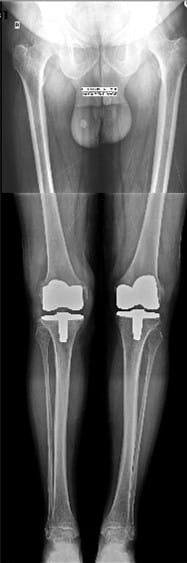

Although there has been an attempt to perform knee replacement in the 19th and early 20th century, Total Knee replacement surgery has come a long way since 1970s with continuous improvement in the design of implants and fixation techniques. Success from Charlney’s hip replacement surgery got surgeons and engineers interested again leading to modern-day implants. It has been successfully being performed worldwide from 1980 onwards. Diseased part of femur and tibia are removed using special instruments and metal implants mimicking design of femur and tibia are inserted using antibiotic-laden polymethyl methacrylate (bone cement). A polyethylene inset is fixed onto the tibial implant thus allowing movement at the knee joint. The undersurface of patella may be replaced with a patellar button in some cases. Due to improved technique and implant design, this surgery has gained immense popularity and has given a new lease of life for the patients suffering with arthritis of the knee joint. Patients can walk comfortably with the help of support following surgery and aren’t dependent on others for day-to-day life activities. Quality of postoperative care in recent times has further boosted the confidence among the patients undergoing this surgery. Patients are taught to strengthen the thigh muscle post-operatively and encouraged to become mobile. Gradually, they learn to climb stairs and later they walk around independently without any aided support. It is recommended that patients should not sit on the floor or squat. This helps maintain the longevity of the implants. As per the American Association of Orthopaedics, success rate of total knee replacement after 15 years is almost 90% and at the end of 25 years is almost 82%.

Your doctor will do clinical examination of knee joint, hip joint, spine and other joints of your body. X-rays of both knees will be performed. Occasionally, MRI of the Knee joint and few blood investigations may be required as per their underlying problem.

In total knee replacement surgery, we remove the damaged area over the femur, tibia and patella in the knee joint. It is replaced it with metal implants which are in the shape of these bones. These metal implants are fixed over your bone with the help of bone cement. Implants come in various sizes and you will get the best fit suited for you.